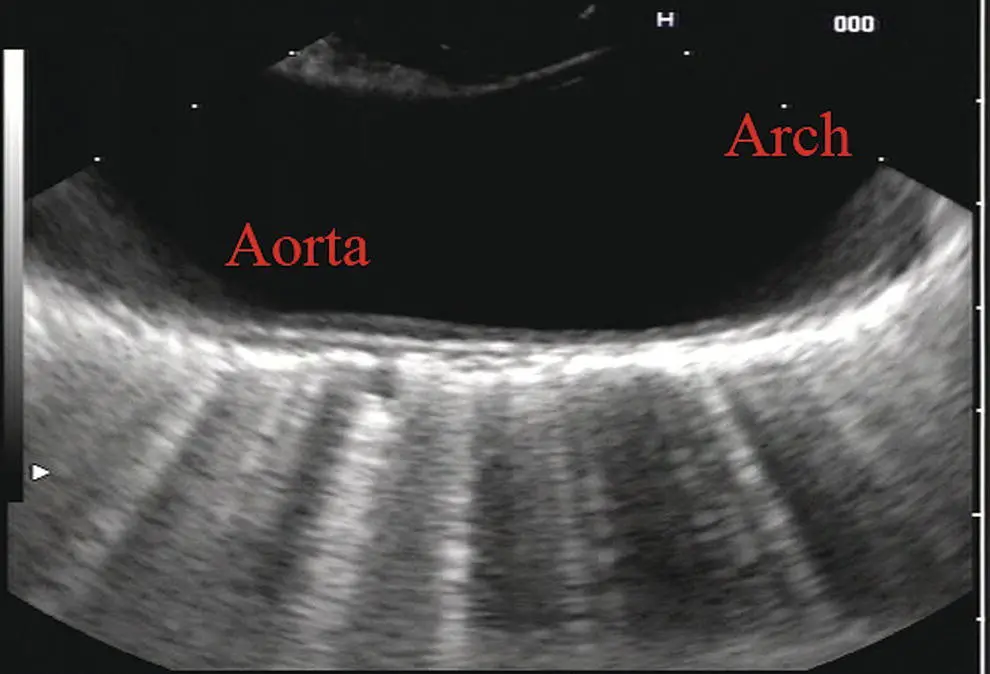

Figure 2.10 Linear array image at the mid aorta.